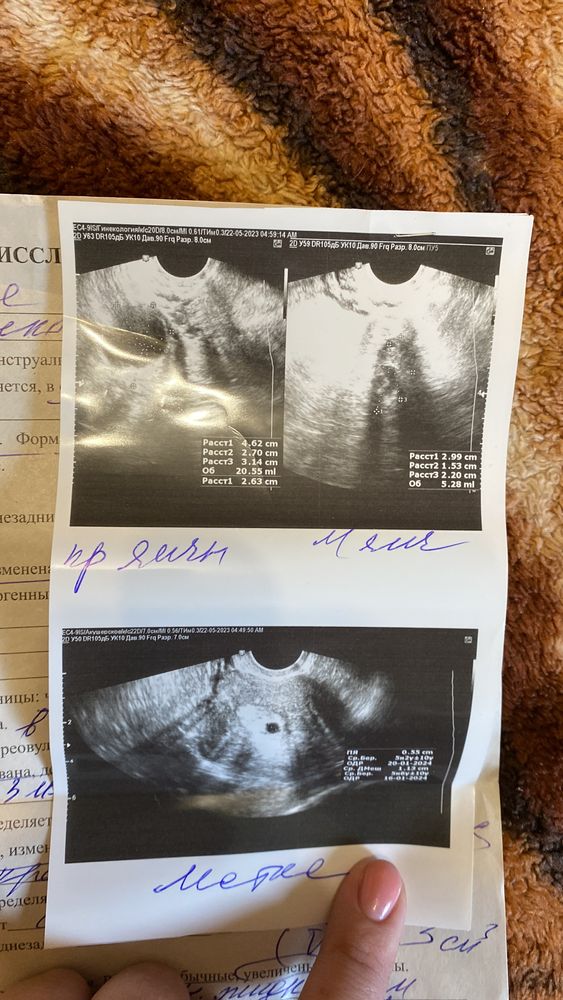

Начнем с того, что мой цикл очень при очень не регулярный. Кроме того, что месячные идут как хотят, больше ни чего не беспокоит. Хотя раньше все было Гуд с ними. Так вот решили мы с мужем, что хотим еще малыша. И так скажем перестали предохраняться. Мес были 25.03.2023, начали стараться над процессом с 13.04. По сей день месячных так и не было. Сделала кучу тестов. Я наверно обогатила все аптеки на районе, заветных полосок так и не увидела. Ходила сегодня к гинекологу и на узи. Увидела образование в матке. Но врач сама не понимает, беременность это или образование какое то. Сказали прийти через 2-3 недели на прием. Я изведусь вся. Прикрепляю фото узи и протокол.ставят срок если это беременность, 5.2 недели. Так то все подходит. Но вот почему тесты до сих пор тогда молчат.